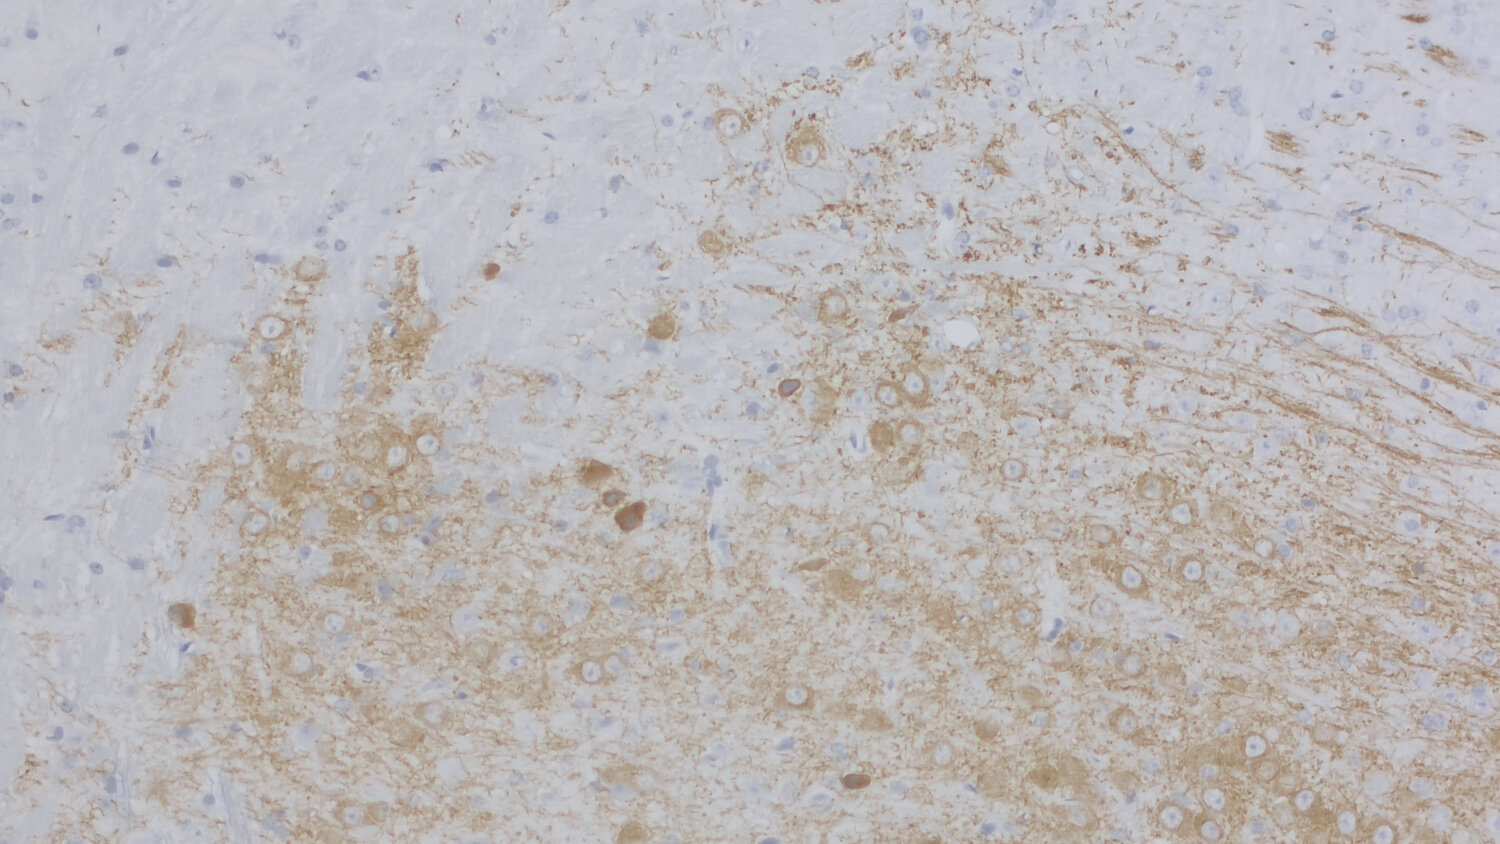

IHC-P (FFPE): 1 : 200 gallery

Immunohistochemistry (IHC-P) of formalin fixed, paraffin embedded (FFPE) tissue (some antibodies require special antigen retrieval steps, please refer to the ”Remarks” section). Immunoreactivity is usually revealed by fluorescence or a chromogenic substrate.

Functionally, DAT contributes to the termination of DA signaling by reuptaking DA, thereby controlling both the duration and magnitude of dopaminergic transmission (4). It is predominantly found in dopaminergic neurons and enriched in regions such as the striatum, substantia nigra, and ventral tegmental area, which are associated with motor control and reward mechanisms (5).